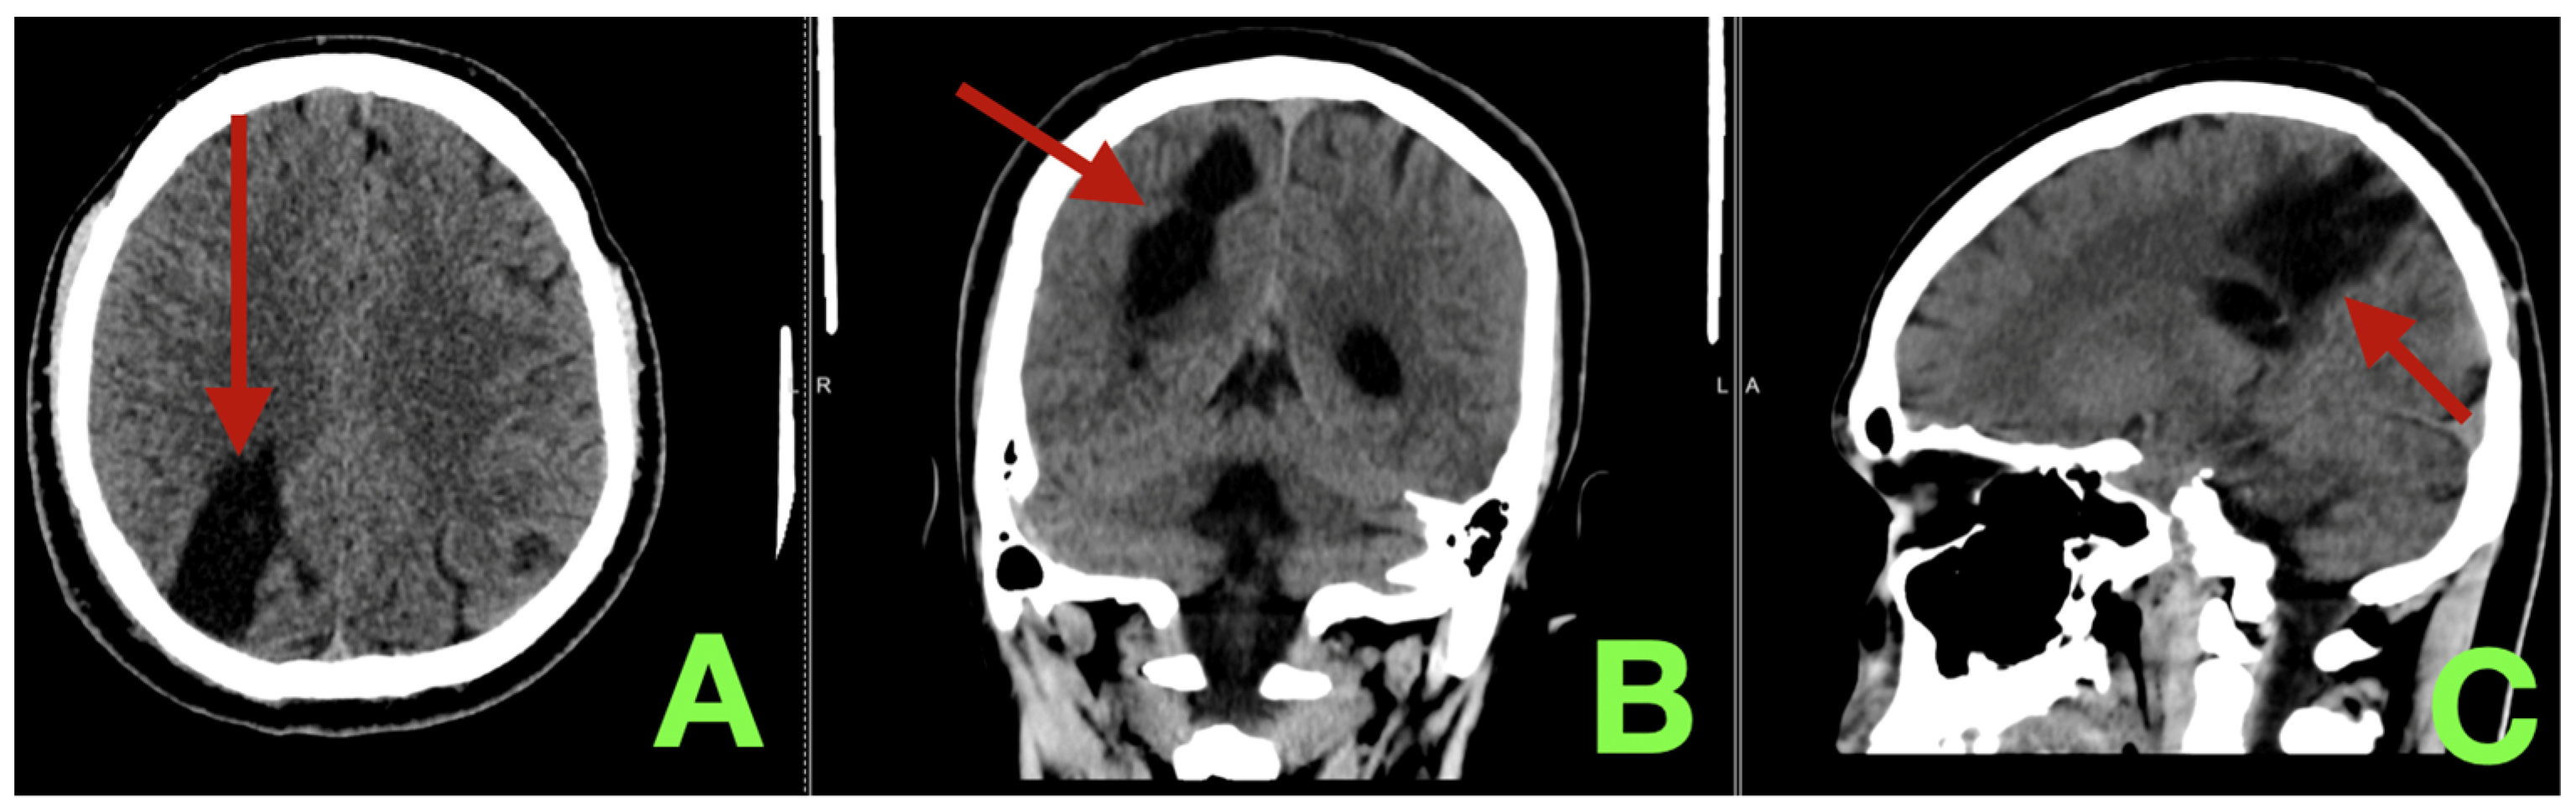

2. Case Presentation